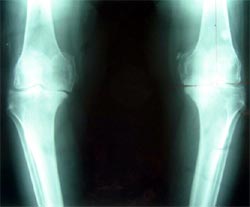

图:膝关节软骨碎裂、磨损,双膝内翻,X线片显示关节间隙消失

患者女性,56岁,双膝骨关节炎15年,双膝屈伸受限,下蹲困难。线片显示膝骨关节炎改变,关节间隙已经消失。膝内翻畸形。行分期人工膝关节置换术。